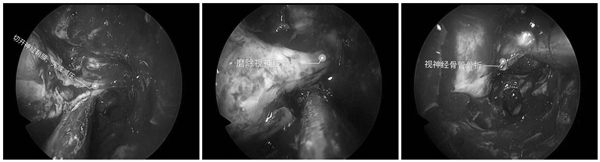

2月19日早10点到达耳鼻咽喉头颈外科病院,孙斌副主任立即查体并以“右侧视神经受损,多发颅底骨折”收住入院,考虑到视神经长时间受压可能会导致患者失明的危险,在已安排10台手术的情况下,孙斌副主任仍坚决要求当日行急诊手术,以抢救患者视力为先。孙主任团队迅速为患者进行各项术前检查,并积极联系放射科、手术麻醉科,同时请眼科会诊,争分夺秒,在13:30患者被接入手术室,给予全身麻醉后在手术导航指引下经鼻内镜行视神经管减压术,患者眼眶骨折、颅底骨折、视神经管骨折,手术历时3小时,清理了碎骨及淤血块,磨除视神经骨管前下璧,切开神经鞘膜,完成减压。手术顺利,患者17点手术结束,返回病房后患者即可清楚视物。